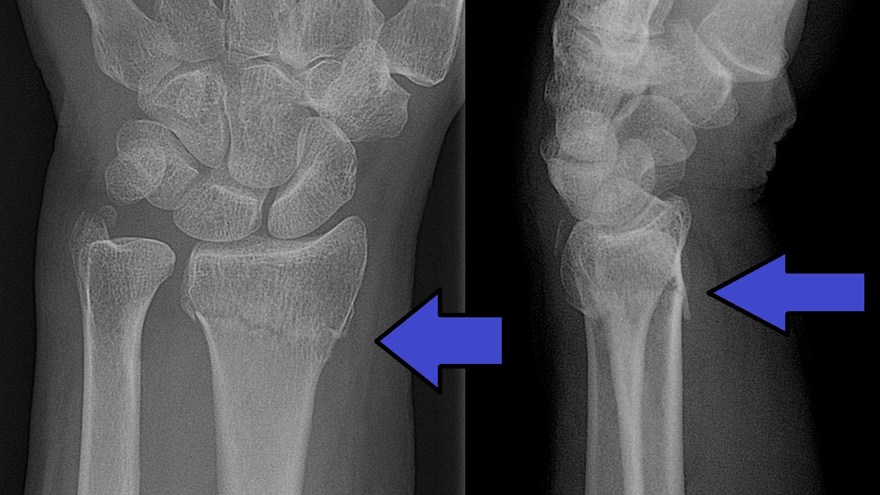

Scaphoideumfraktur

Symtom

Palpationsömhet i fossa Tabatiére, smärta vid axialt kompression av tummen samt vid dorsalextension respektive radialdeviation av handleden.

Drabbar ofta yngre individer i samband med sportutövning eller efter annat kraftigt dorsalextensionsvåld. Frakturen är ofta svår att identifiera på slätröntgen varför upprepade undersökningar och/eller CT/MR kan behövas.

Scaphoideum är dåligt vaskulariserad och ofta läker dessa frakturer (ffa proximala polfrakturer) långsamt; 3 månader i gips är normaltid! Gipsen skall immobilisera tumbas, handled och begränsa armens pro-supination. Utebliven läkning (pseudartros) är relativt vanligt och risken ökar om frakturen inte immobiliseras från skadetillfället.

Vid misstanke om scaphoideumfraktur (adekvat trauma, ömhet i fossa Tabatiére)

- Immobilisera i scaphoideumgips även om röntgen bedöms normal.

- Beställ då röntgenkontroll (utan gips) efter 10-14 dagar! Om röntgen är u a även efter 2 veckor, men status kvarstår: ordna snar MR- eller CT-undersökning!